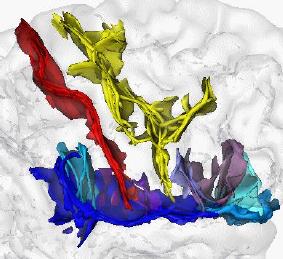

A Statistical Study of the Cardiac Diffusion Tensor Images

While the main geometrical arrangement of myofibers has been known for decades, its variability between subjects and species still remains largely unknown. Understanding this variability is not only important for a better description of physiological principles but also for the planning of patient-specific cardiac therapies. Furthermore, the knowledge of the relation between the myocardium shape and its myofiber structure is an important and required stage towards the construction of computational models of the heart since the fiber orientation plays a key role when simulating the electrical and mechanical function of the heart. The knowledge about fibre orientation has been recently eased with the use of Diffusion Tensor Imaging (DTI) since there is a correlation between the myocardium fibre structure and diffusion tensors. DTI also has the advantage to provide directly this information in 3D with a high resolution, unfortunately it is not available in vivo due to the cardiac motion. A statistical study of ex vivo cardiac DTI will help in understanding the cardiac fibre structure and in modeling the electromechanical behavior of the heart.

While the main geometrical arrangement of myofibers has been known for decades, its variability between subjects and species still remains largely unknown. Understanding this variability is not only important for a better description of physiological principles but also for the planning of patient-specific cardiac therapies. Furthermore, the knowledge of the relation between the myocardium shape and its myofiber structure is an important and required stage towards the construction of computational models of the heart since the fiber orientation plays a key role when simulating the electrical and mechanical function of the heart. The knowledge about fibre orientation has been recently eased with the use of Diffusion Tensor Imaging (DTI) since there is a correlation between the myocardium fibre structure and diffusion tensors. DTI also has the advantage to provide directly this information in 3D with a high resolution, unfortunately it is not available in vivo due to the cardiac motion. A statistical study of ex vivo cardiac DTI will help in understanding the cardiac fibre structure and in modeling the electromechanical behavior of the heart.

Tensor computing

The emergence of diffusion tensor imaging (DTI) in the medical imaging community led to challenges in mathematics in order to manipulate 2nd order symmetric positive-defined matrices, so called tensors. In DT-MRI, each voxel of the brain contains a tensor, which is the 2nd order approximation of the brownian motion of water at this specific location. As water tends to move along oriented tissues (such as white matter neural fibers) diffusion tensors are likely to be aligned with the underlying structures. Due to the noise corrupting the data, the tensor field needs adequate post-processing before any further analysis. However, one cannot manipulate tensors like scalars (the tensor space is not a vector space). We used results in differential geometry to manipulate tensors while ensuring to remain on the tensor space, i.e. to keep the positive-defined constrain verified at all time. Applications are: tensor field regularization (PDE, etc.) and shape statistics (see the collaboration Epidaure-LONI).

The emergence of diffusion tensor imaging (DTI) in the medical imaging community led to challenges in mathematics in order to manipulate 2nd order symmetric positive-defined matrices, so called tensors. In DT-MRI, each voxel of the brain contains a tensor, which is the 2nd order approximation of the brownian motion of water at this specific location. As water tends to move along oriented tissues (such as white matter neural fibers) diffusion tensors are likely to be aligned with the underlying structures. Due to the noise corrupting the data, the tensor field needs adequate post-processing before any further analysis. However, one cannot manipulate tensors like scalars (the tensor space is not a vector space). We used results in differential geometry to manipulate tensors while ensuring to remain on the tensor space, i.e. to keep the positive-defined constrain verified at all time. Applications are: tensor field regularization (PDE, etc.) and shape statistics (see the collaboration Epidaure-LONI).